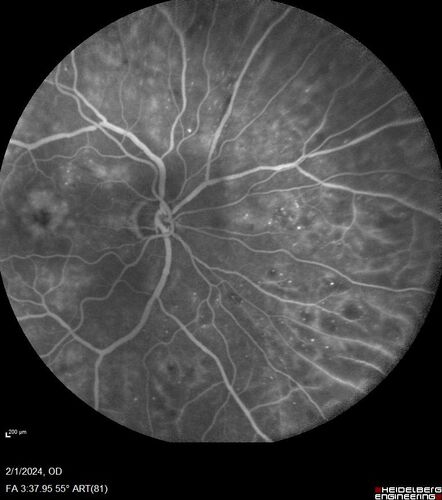

Chronic Myelogenous Leukemia and Diabetic Macular Edema

71 year old female with 3 months of vision loss and not feeling well.  She has been bruising on her legs.  Her vision was 20/100 in each eye with macular edema.  She was treated with Avastin and her CBC was checked.  She had a WBC of 267 thousand and was diagnosed with CML.